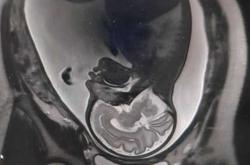

备孕做B超后是可以怀孕的哈。B超用的是超声波,没有辐射,不会影响卵子和精子的质量,所以做完检查当月就能正常备孕。而且做B超还能看看子宫里的情况,比如有没有肌瘤、息肉,或者内膜厚度够不够,要是有问题...